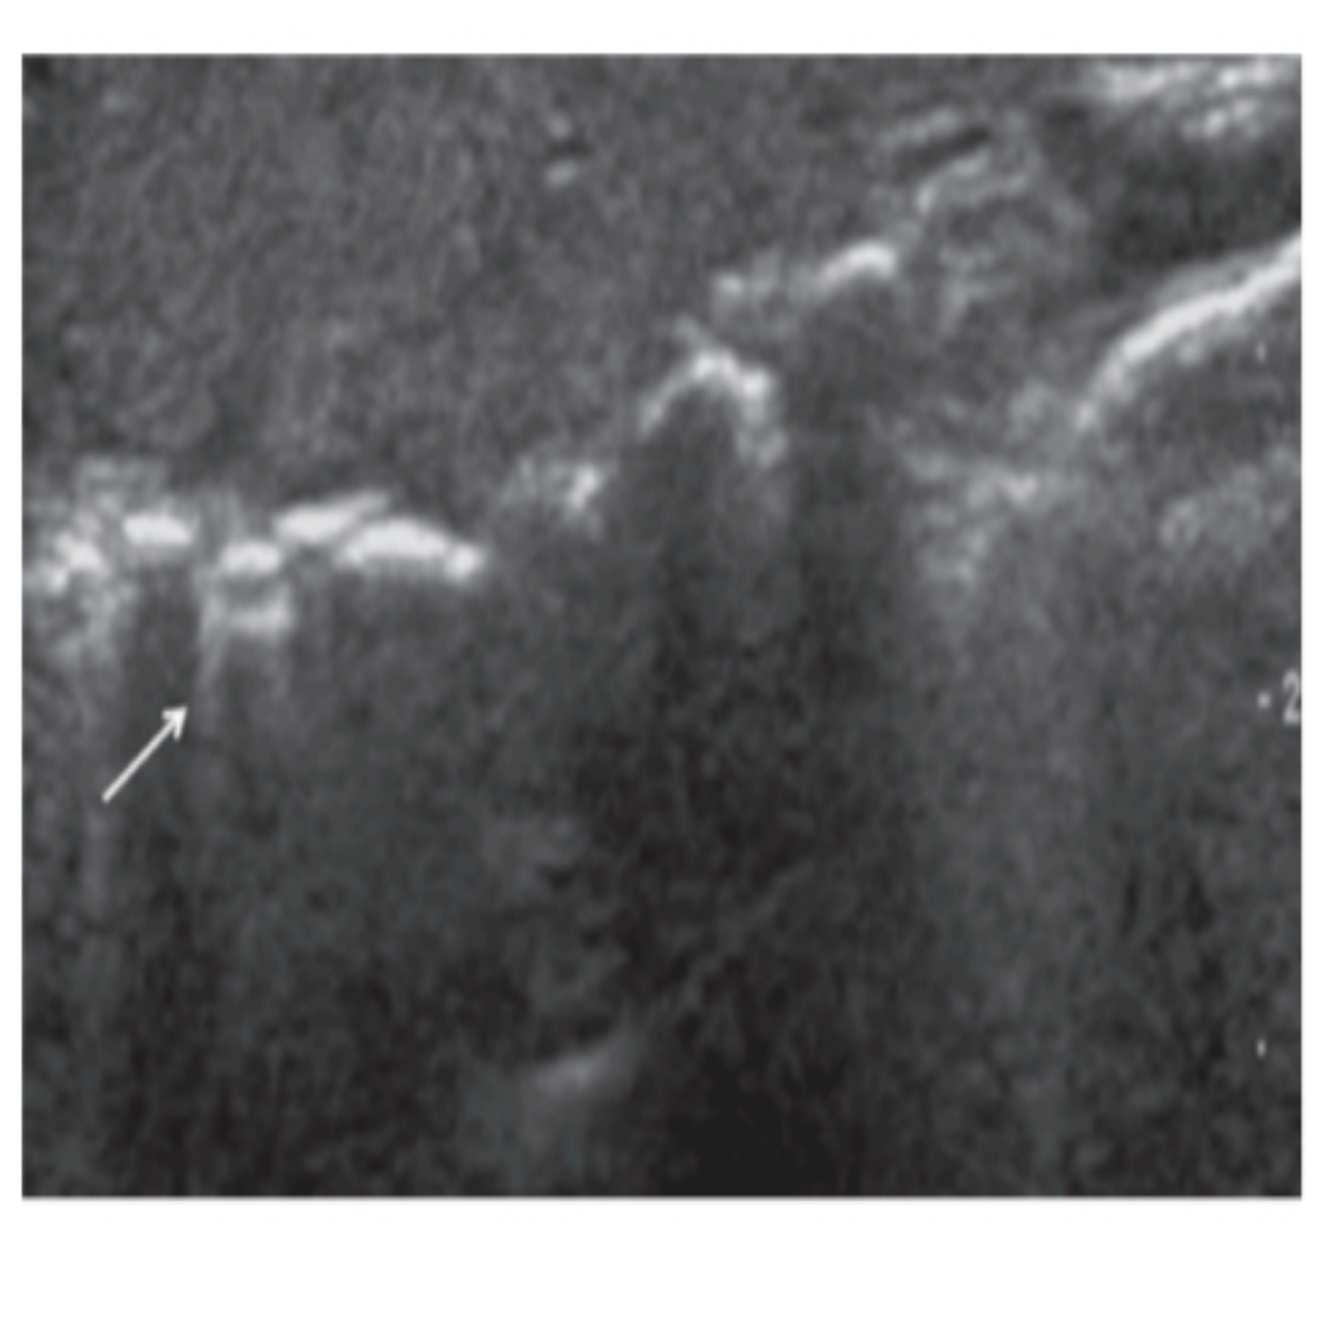

21

Q

POCUS PULMONAR: Qual o nome deste achado?

A

LINHAS Z

How well did you know this?